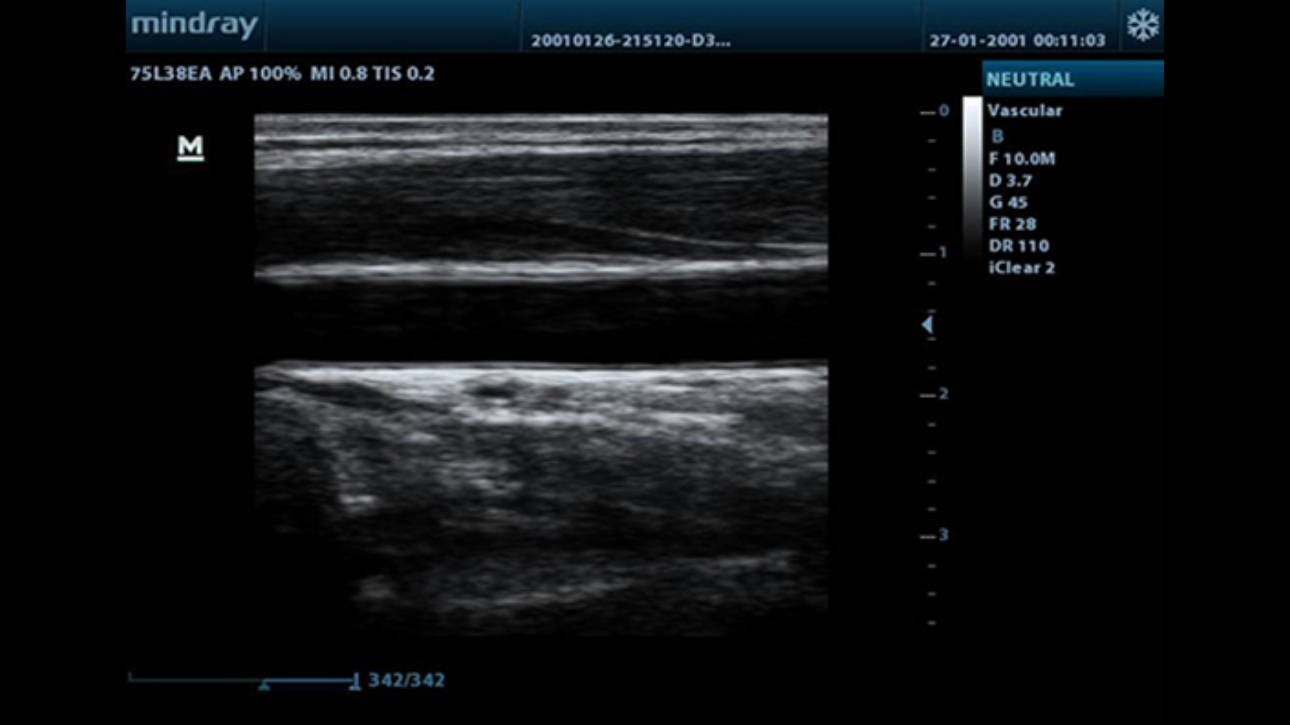

Tissue Harmonic Imaging

Utilizing second harmonics generated from tissue boundary layers, THI significantly enhances contrast resolution and improves image quality especially for technically difficult subjects.

iClear?

Gain improved image quality based on auto structure detection.

- Sharper & Continuous Edges

- Smooth Uniform Tissues

- Cleaner ŌĆśno echo areasŌĆś